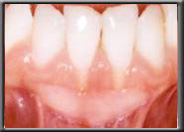

Gum Recession

Some people are born without sufficient attached gingiva to prevent the muscle in the alveolar mucosa from pulling the gum down. In these cases the gum slowly continues to recede over time, even though the patient may be very conscientious with their oral health. This is not an infection, as is seen with periodontal disease, but rather simply an anatomic condition. Unfortunately, bone recession is occurring at the same time the gum is receding. This is because the bone, which is just under the gum, will not allow itself to become exposed to the oral cavity and moves down with the gum.

A lack of attached gingiva is sometimes associated with a high frenum attachment, which exaggerates the pull on the gum margin. A frenum is a naturally occurring muscle attachment, normally seen between the front teeth (either upper or lower). It is normal to have a frenum, but it should not pull on the gum margin or recession will occur. If pulling is seen, the frenum is surgically released from the gum with a frenectomy. Often a new band of hard gum is also added to re-establish an adequate amount of attached gingiva (see below).

With the wear and tear of time, even normal attached gum can be worn away, generally from vigorous brushing. This often happens in people with naturally thin tissues, or when the tissues have been stretched during orthodontics. If there is still adequate attached gum to act as a barrier to the muscle, the treatment for recession is to ensure further damage isn't done when brushing. However, if the attached gum is worn to the point where it cannot resist the constant pull of the mucosa, recession will continue unless a new hard band of gum is placed. Unchecked, the recession can cause tooth loss as the bone recedes with the tissue and tooth support weakens.